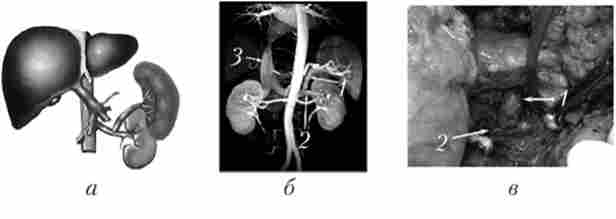

Мал. 17.9. Проксимальний спленоренальний анастомоз:

а - схема; б - ангіограма; в - интраоперационная фотографія; 1 - селезеночная вена; 2 - ліва ниркова вена

Мезентерікокавальний // - анастомоз

Мал. 17.10. Мезентерікокавальний // - анастомоз:

а - схема; б - магнітно-резонансна ангіограма; в - интраоперационная фотографія;

В даний час парціальні портокавальние шунти малого діаметра широко використовуються для профілактики і лікування кровотеч з варикозно-розширених вен стравоходу, здійснюючи дозовану декомпресію портальної системи і зберігаючи при цьому гепатопетальний кровотік.